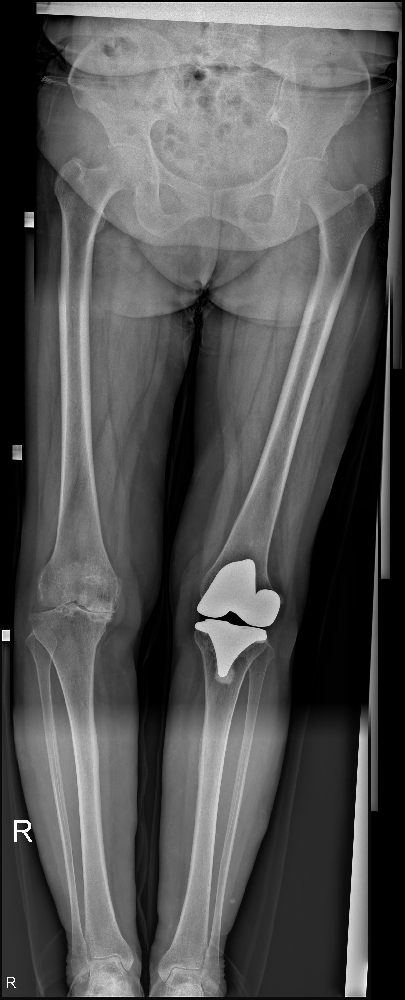

終于,在被送往市中區(qū)誠(chéng)德骨科醫(yī)院接受進(jìn)一步檢查后,張廣美接受了雙側(cè)全膝關(guān)節(jié)置換手術(shù),并且術(shù)后的恢復(fù)效果非常良好。

雙側(cè)全膝關(guān)節(jié)置換手術(shù)是一種常見的治療方法,主要是通過將病變的膝關(guān)節(jié)組織替換為人工關(guān)節(jié)來(lái)改善患者的運(yùn)動(dòng)功能和減輕關(guān)節(jié)疼痛。這種手術(shù)旨在重建膝關(guān)節(jié)的穩(wěn)定性和功能,提高患者的生活質(zhì)量。